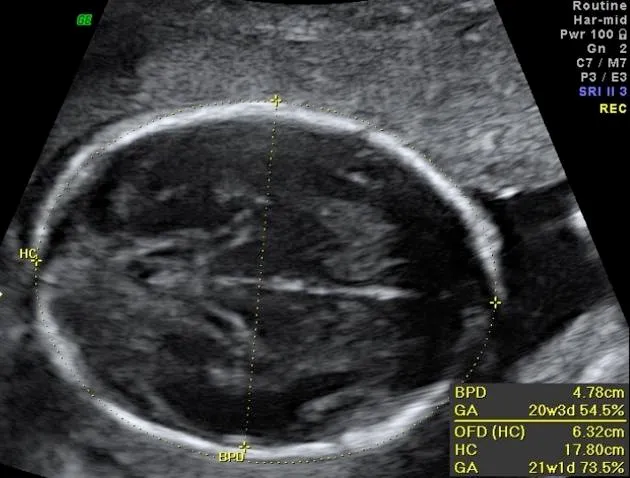

- Biparietal Diameter (BPD): Widest diameter of the fetal head.

- Head Circumference (HC): Measured at the same level as BPD.